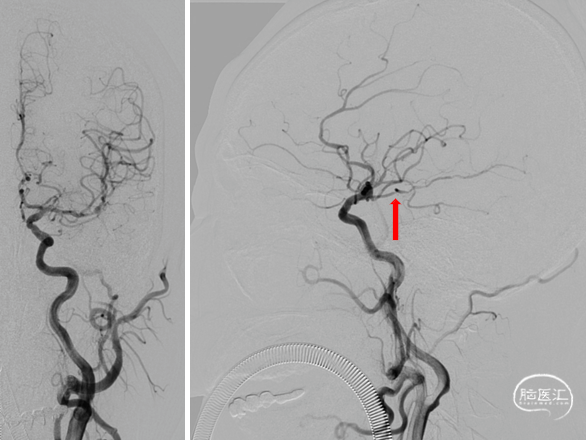

椎动脉后循环旋转造影

造影示:右侧优势椎,经右侧椎动脉导弯造影,双侧胚胎型大脑后动脉。

基底动脉狭窄位于双侧AICA开口处,且无双侧PICA,其供血区由双侧AICA、SCA分支代偿供血。

术中如何扩张基底动脉的同时保护双侧AICA通畅是手术成功的关键。